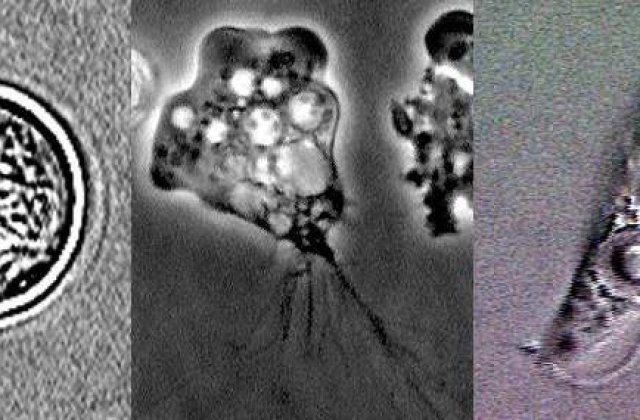

- Amiba patrunde in corpul oamenilor prin nas, de obicei dupa ce persoana a inotat sau s-a scufundat in apa dulce calda, cum ar lacuri, iazuri, rauri sau izvoare termale. Apoi, aceasta se infiltreaza in creierul victimelor.

Amiba cauzeaza foarte rar infectii in randul oamenilor, iar 95% dintre cazuri sunt fatale. Simptomele includ dureri de cap, febra, stari de greata si dureri de gat, infectia cu amiba provocand aproape intotdeauna meningita. Dupa o saptamana de la contaminare, persoanele manifesta probleme de echilibru, confuzie, convulsii si se ajunge chiar la deces.